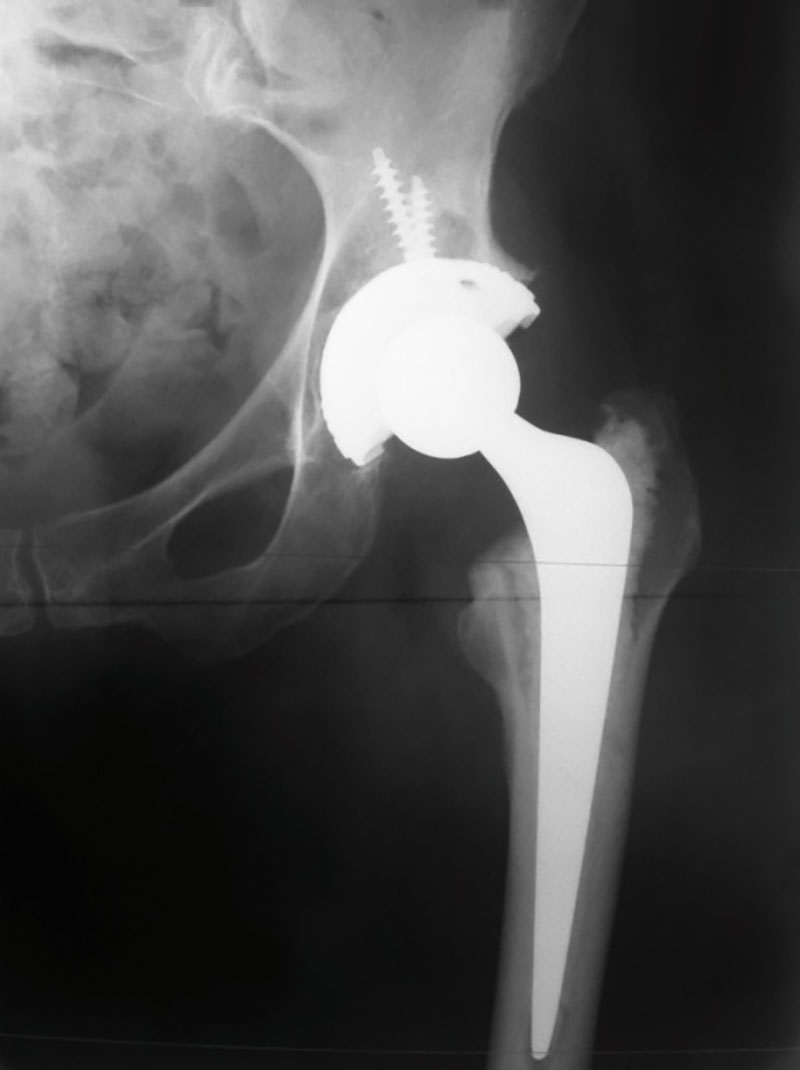

(Left Hip Arthritis)

(Left total hip Replacement post-operative X-ray)

SURGERY

Through an incision approximately 12-15cm long centred over the side of the hip and curving gently towards the buttock, the hip joint can be entered with minimal trauma to the surrounding muscles. The hip is dislocated and the femur bone is cut through its neck to expose both the pelvic and leg sides of the joint. Depending upon the quality of the bone and the age of the patient either a cemented or cementless component is fixed to the pelvis and similarly to the femur. The ball and socket mechanism of the joint is then reconstructed with either a metal on plastic (polyethylene) articulation or ceramic on ceramic articulation. Computer navigation may be used to ensure that the leg length obtained is correct and the orientation of the components is optimal to provide for maximum range of motion of the new hip.